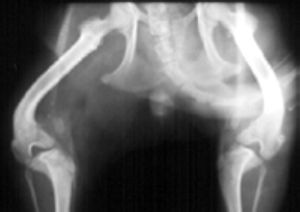

CHD has been called inherited, a developmental disease, and most accurately in the author's opinion, a "moderately heritable disease". CHD is a multifactorial disease with part of its cause being from genetic influences (estimated at 25%-80%) and part from environmental influences.